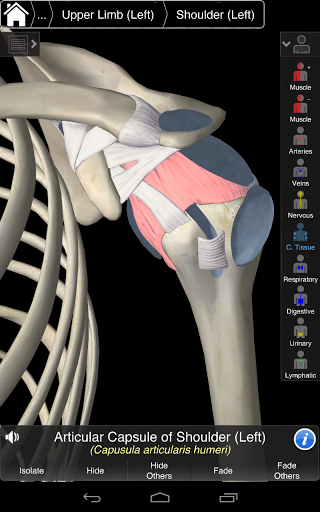

Essential Anatomy 3 represents the latest in groundbreaking 3D technology and innovative design. A cutting edge 3D graphics engine, custom built by 3D4Medical from the ground up, powers a highly-detailed anatomical model and delivers outstanding quality graphics that no other competitor can achieve.

The app represents a unique approach to learning general anatomy. The graphics are unparalleled and make learning, through the use of informative content and innovative features, a rich and engaging experience.

NEW 3D TECHNOLOGY

Essential Anatomy 3 is responsive, visually stunning and effortless. The app is fully 3D, meaning that you can view any anatomic structure in isolation, as well as from any angle.

---- Over 4,000 highly detailed anatomical structures

---- Latin nomenclature for each anatomical structure